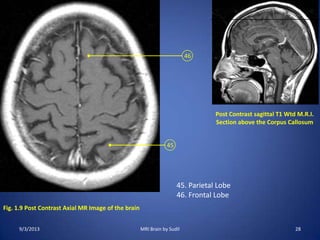

Fig. 1.1 Post Contrast Axial MR Image of the brain

Post Contrast sagittal T1 Weighted

M.R.I.

Section at the level of Foramen

Magnum

1. Cisterna Magna

2. Cervical Cord

3. Nasopharynx

4. Mandible

5. Maxillary Sinus